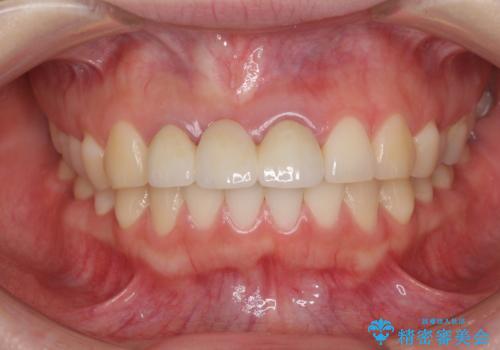

- 他院で装着したばかりの前歯のブリッジが気に入らず、作り替えを希望して来院された患者様です。

前院では、土台の金属を除去することは不可能であると言われたとのことでした。金属の土台が残っているとセラミックにグレーの金属色が透けて見えてしまうため、拡大鏡やマイクロスコープを用いて丁寧に除去し、天然歯の色に近いファイバーコアを植立することとしました。

また、歯とクラウンの境目が合っていない部分が多く、歯肉からの出血が認められました。

金属色の透けた感じも歯肉からの出血もなくなり、自然な仕上がりの前歯となったので、患者様には大変満足していただきました。